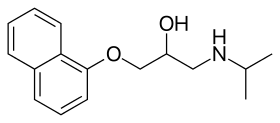

Propanolamines are a class of chemical compounds, many of which are pharmaceutical drugs. They are amino alcohols that are derivatives of 1-amino-2-propanol.[1]

Propanolamines include: